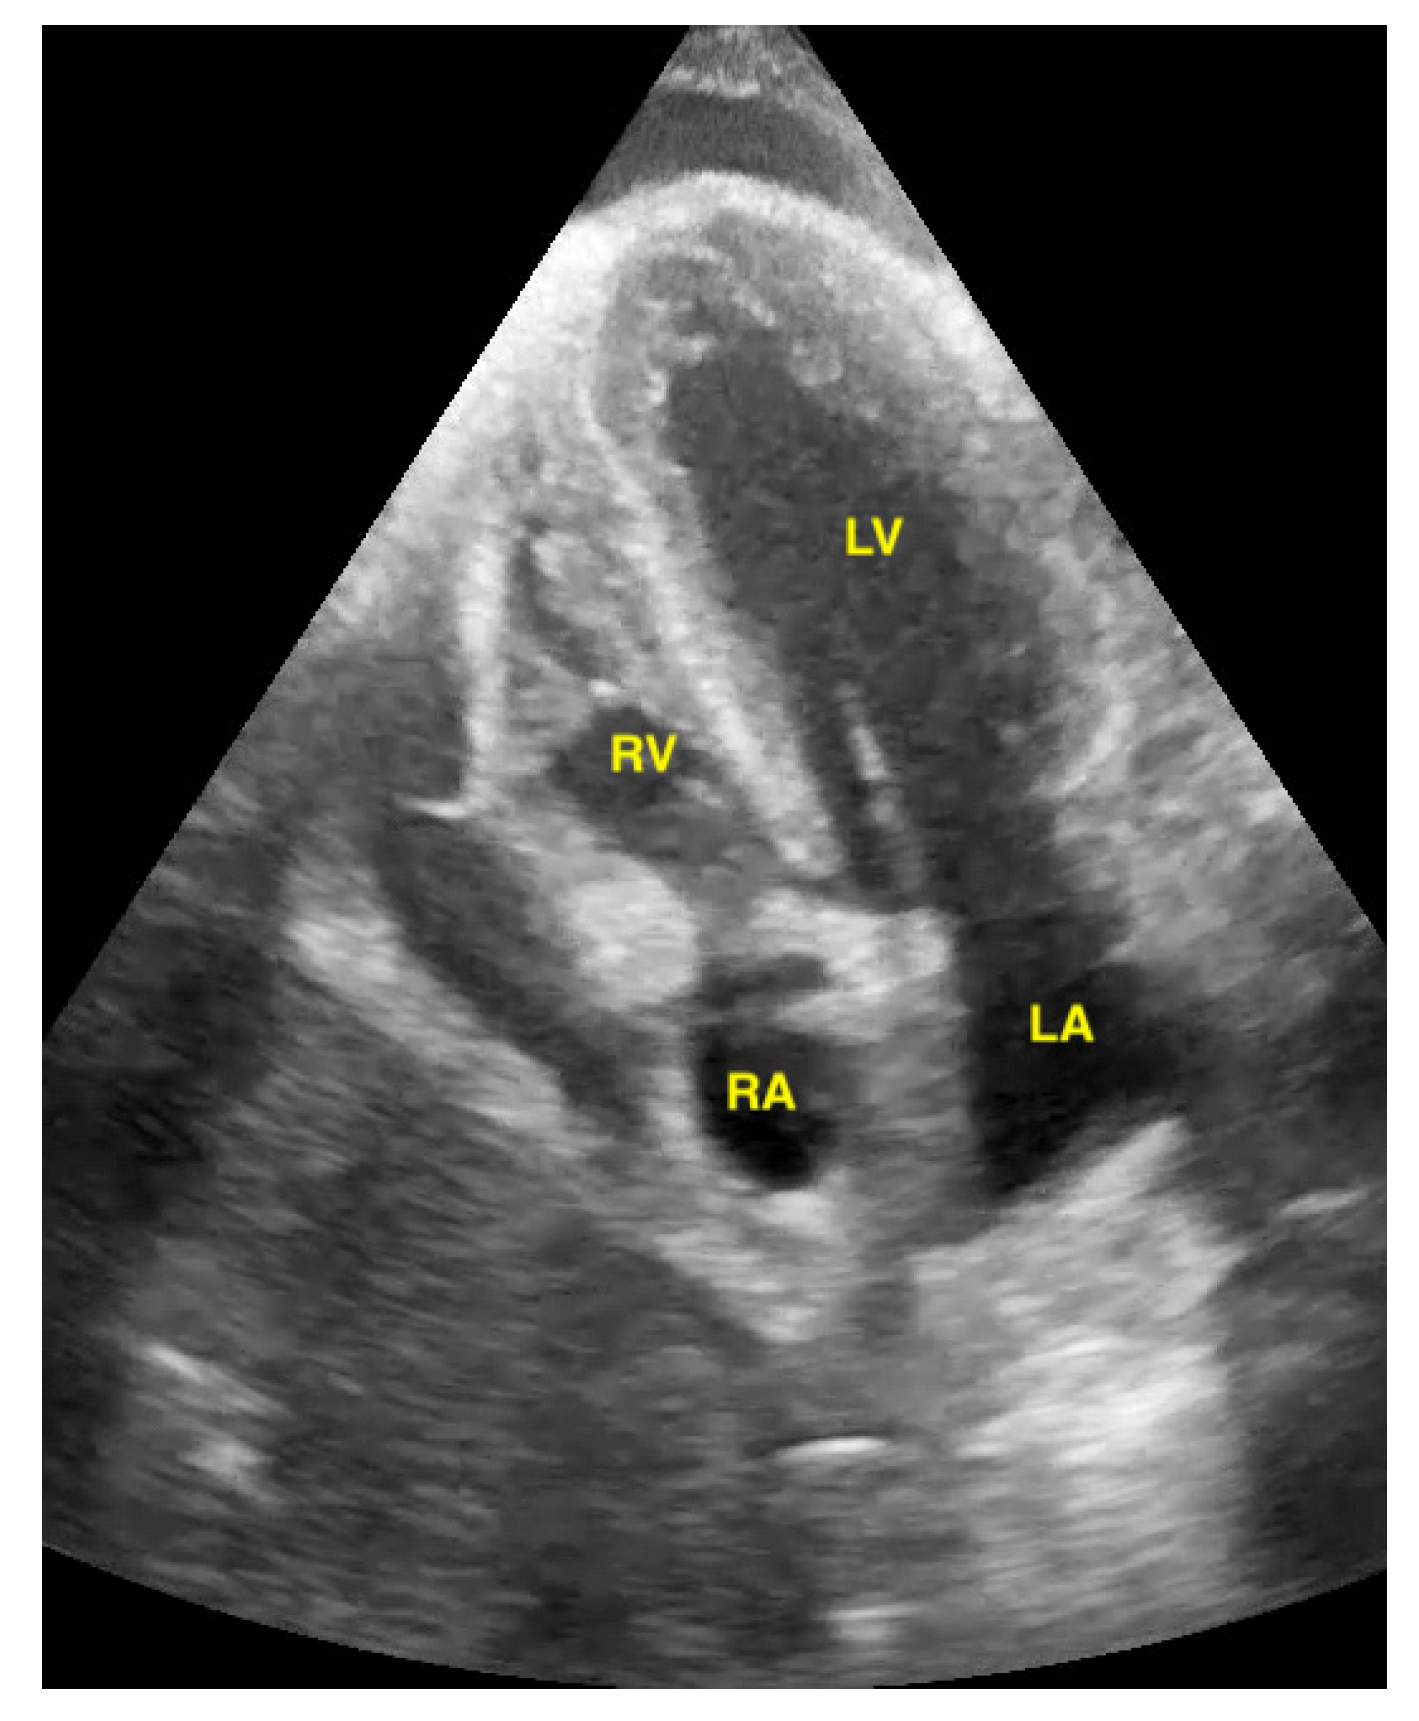

Pericardial effusions are best identified with a convex or sector probe in the subxiphoid or parasternal view. While it is important to simply note whether an effusion is present, sonographic and clinical (hypotension and tachycardia) evidence of cardiac tamponade should be sought. These include diastolic collapse of the right atrium free wall, followed by free wall collapse of the right ventricle as tamponade worsens. Both the apical and subcostal four-chamber views are ideal for this assessment. However, the subcostal window allows for a rapid transition to the proximal IVC view, which is dilated (>2 cm) and does not vary with respiration in cases of cardiac tamponade. Although many cases of medium and large pericardial effusions are obvious on ultrasound, there are notable exceptions. These include some hemorrhagic effusions which show significant coagulation, thus appearing echogenic on ultrasound, leading to frequent confusion with an epicardial fat pad or even a portion of the myocardial wall. Conversely, some epicardial fat pads may be confused with pericardial effusions, especially by novices. Differentiating between the two is easy by using anatomical knowledge. An epicardial fat pad does not extend enough inferiorly to be seen on a longitudinal IVC inlet view, while a pericardial effusion will in virtually all cases (Figure 7, Figure 8, Figure 9 and Figure 10).

Figure 7.

Pericardial effusion in parasternal long-axis view.

Figure 9.

Pericardial effusion in apical four chamber view compresses the right atrium slightly (RA = right atrium, LA = left atrium, RV = right ventricle, LV = left ventricle).